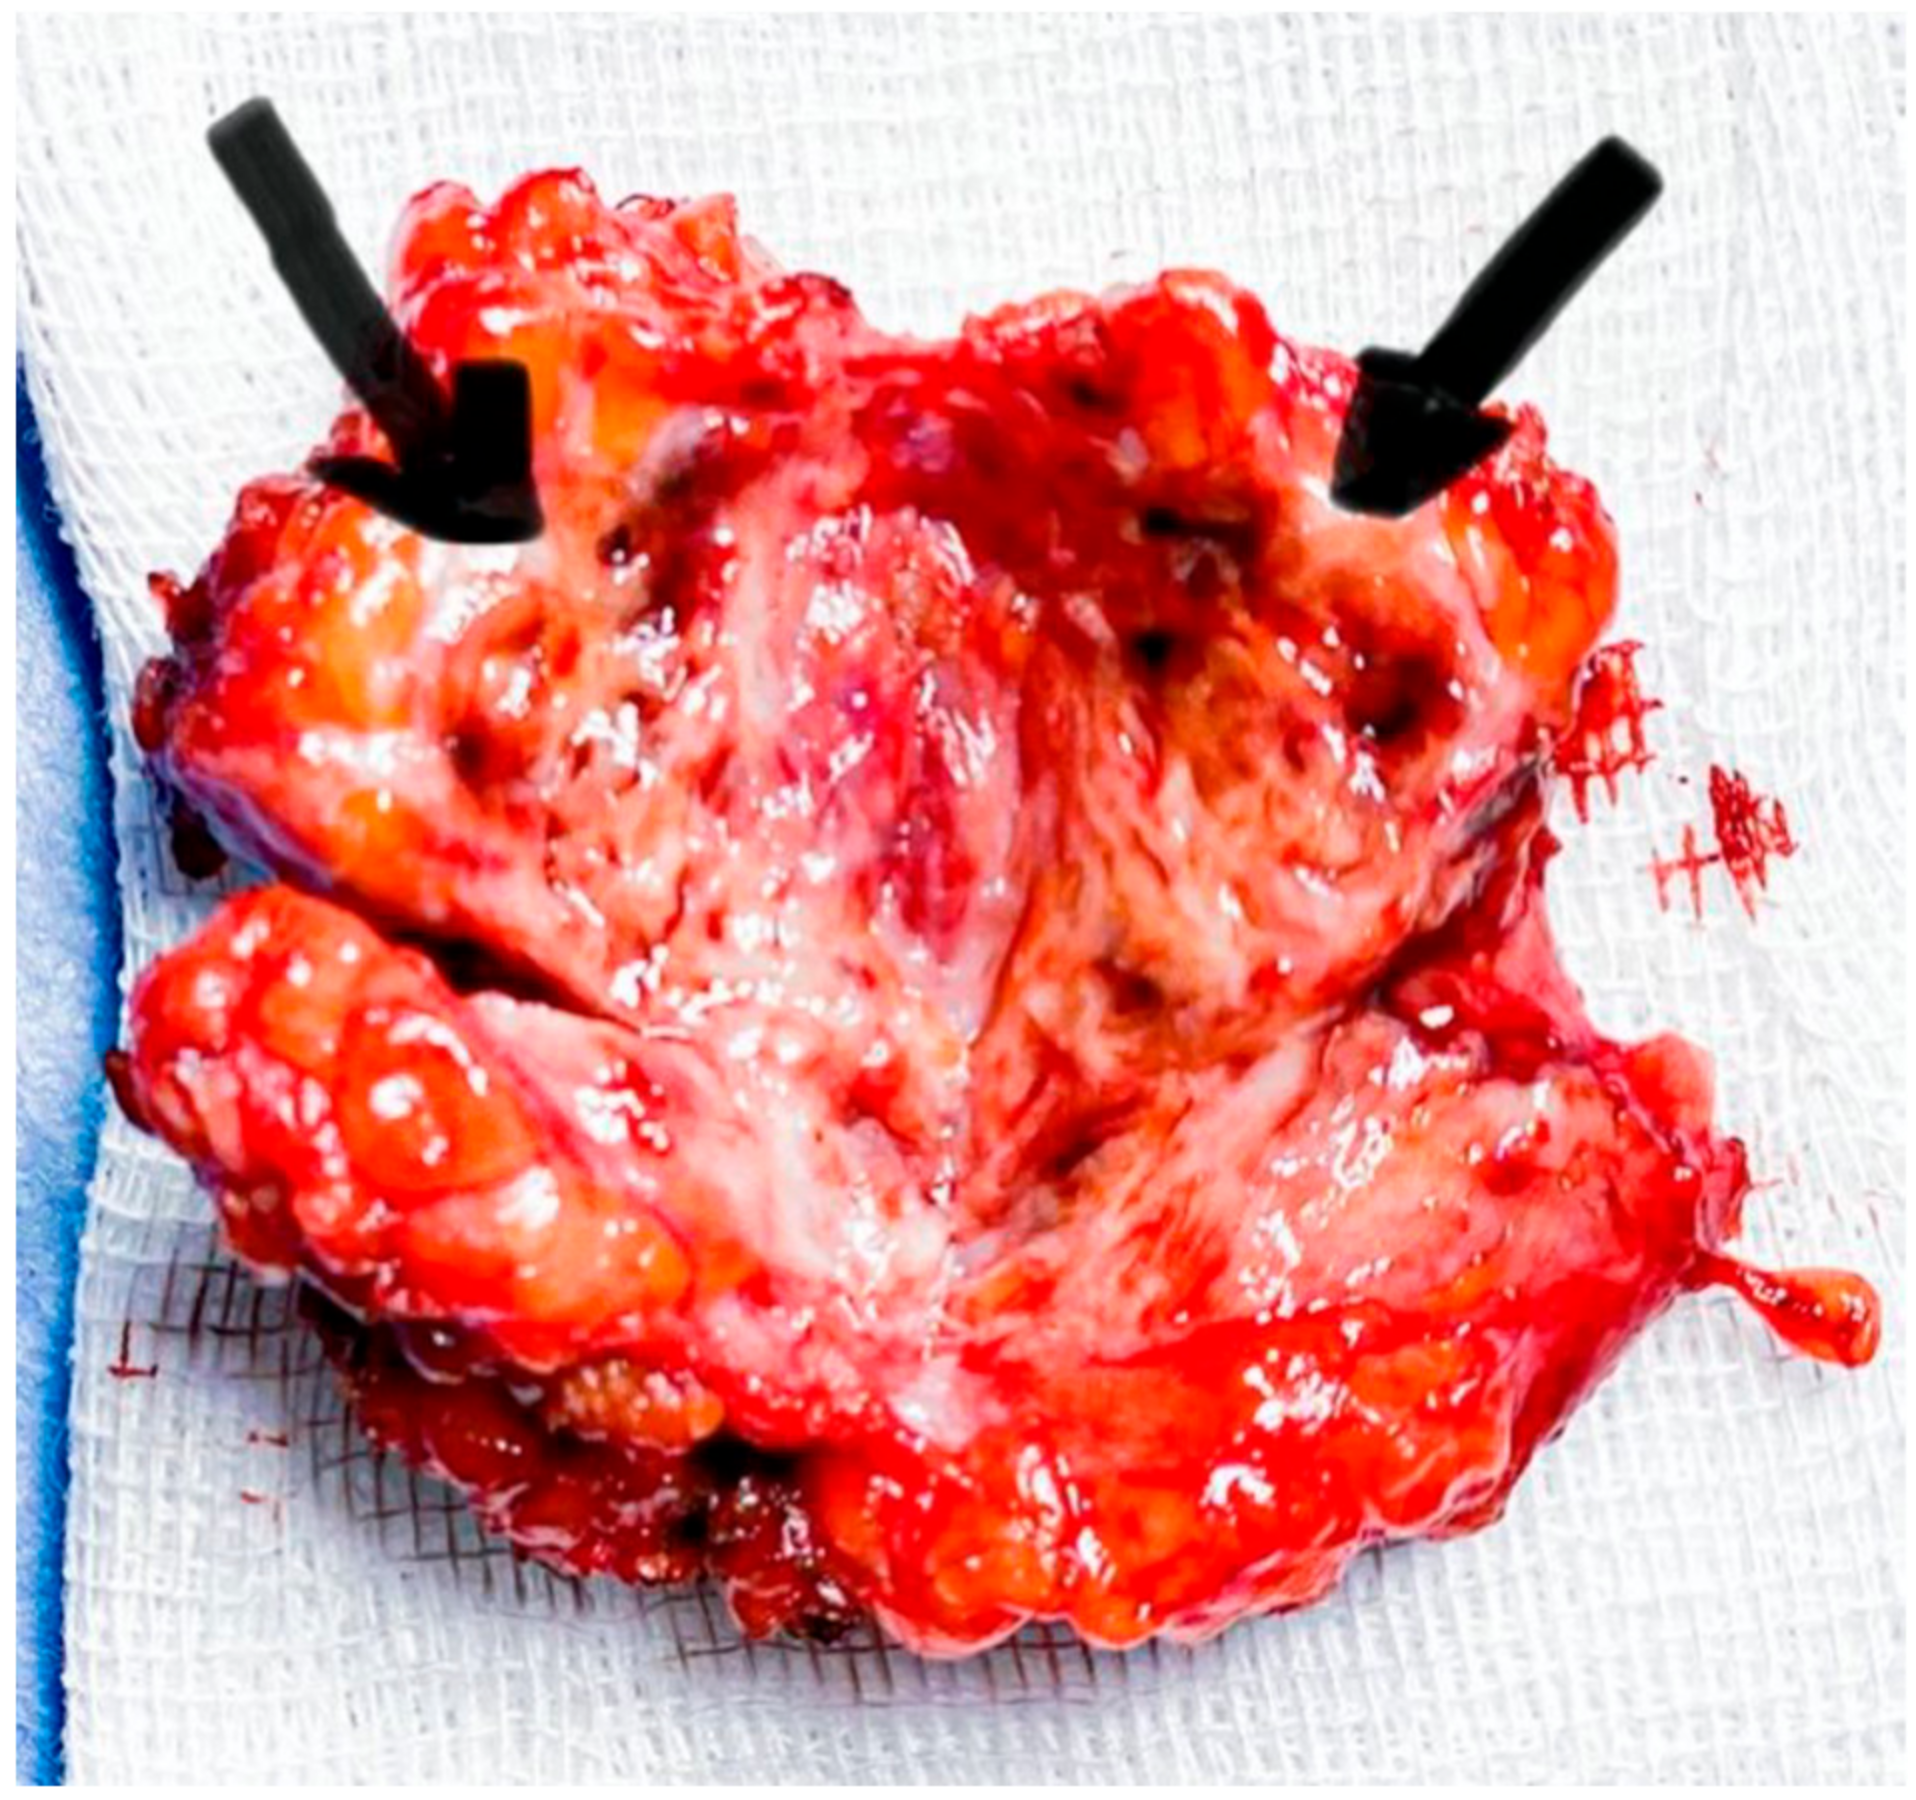

2.1. Case 1